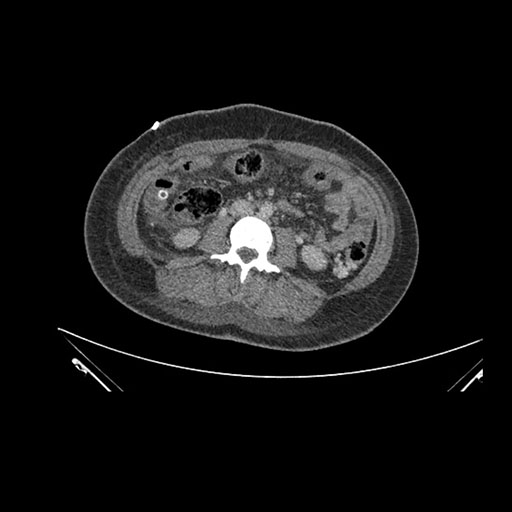

Imaging Analysis

Look through the patient's CT scan to identify any areas of concern for the necessary procedure.

Axial Venous

Coronal Venous

Based on initial findings, which issue(s) would you be most concerned about?